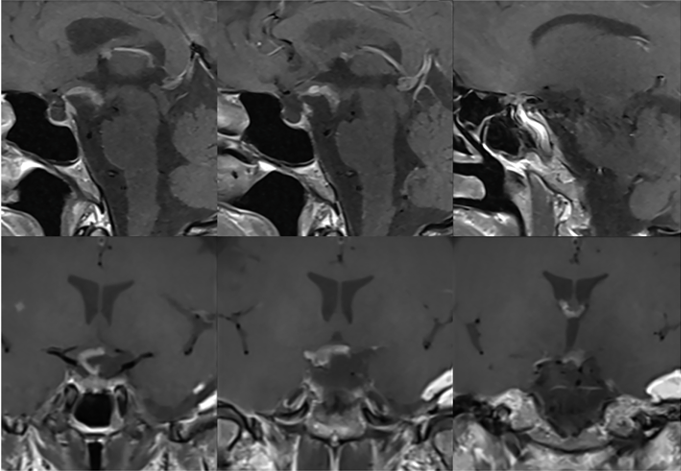

挑战环节一体现在肿瘤与垂体组织、视神经结构的粘连程度严重方面。磁共振影像显示,安娜的肿瘤呈现出球形特点,占据了垂体漏斗后部位置及鞍上间隙区域,与垂体柄区域和正常垂体组织呈现紧密相邻的解剖关系。

视交叉结构因为肿瘤的压迫作用已经出现明显的移位变形、组织变薄的状态改变,动眼神经同样受到一定程度的牵拉影响。肿瘤还与颈内动脉管壁、后交通动脉管壁、大脑前动脉管壁和大脑后动脉管壁呈现紧密粘连状态,术中进行剥离操作的难度极大,稍有不慎就可能引发大出血的紧急状况。

术后六个月进行随访检查时,影像结果显示残余的肿瘤组织没有任何的生长迹象表现。安娜的视力状况逐渐恢复良好状态,又能清晰地看见这个多彩的世界了。